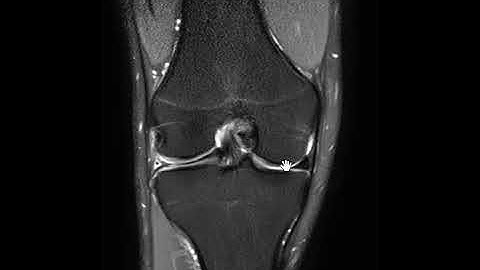

Bucket Handle Meniscus Tears